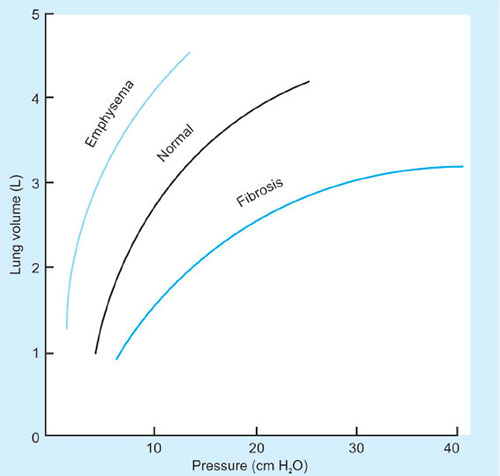

Elastic recoil is usually measured in terms of compliance.

Compliance is defined as the volume change per unit pressure change.

Compliance = ΔV/ΔP

It is classified into chest wall, lung or total lung compliance (distensibility).

Normally, it equals 200 mL/cm H2O

There are 2 types of compliance: static and dynamic

Static compliance is measured during plateau pressure.

Dynamic compliance varies and is calculated with measurement of tidal volume at a given intrathoracic pressure during which there is airflow through the lungs at any point during inspiration or expiration.

A variety of factors affect this like lung volume, pulmonary blood volume, extravascular lung water and pathological processes (inflammation, fibrosis)

Compliance can be measured by inserting an esophageal probe into a cooperative patient, the patient inhales and exhales to a set volume. At each volume the intrapleural pressure is estimated using the esophageal probe. A pressure volume curve can then be plotted. If during the measurement process no gas flow occurs at each set volume then this is static compliance. (Gas flow ceases and equilibration occurs.) If gas flow continues throughout measurement then this is dynamic compliance.

Compliance increases in old age and emphysema as elastic lung tissue is destroyed. It is decreased in pulmonary fibrosis, pulmonary edema, atelectasis and in the extremes of lung volume.

Factors affecting compliance are:

Disease: In atelectasis, when the lung is relatively stiff, the point of balance (resting expiratory volume) will be reached at a lower lung volume, as there will be greater pull inwards; this will predispose to further atelectasis. The excessively compliant emphysematous lung has less elastic recoil; resting expiratory volume will then be greater, since the natural tendency for the chest wall to expand is maintained.

Age: The immature lung in the infant is less elastic than in adulthood. Elasticity is highest in young adults and it decreases slowly with advancing age—lung compliance is therefore lowest in young adults. Chest wall compliance is highest at birth and slowly declines with age.

Posture: Thoracic compliance is lower in the supine position, as the gravitational pull of the abdomen, which existed in the upright position, is reversed and the diaphragm is pushed into the chest by the abdominal contents.

Anesthesia: Several factors (supine position, airway closure, changes in intrathoracic blood volume, accumulation of fluid, direct effect of drugs, altered muscle tone, external pressure) influence compliance under anesthesia; generally compliance is decreased.

Obesity: The effect is compounded by supine or lithotomy position.